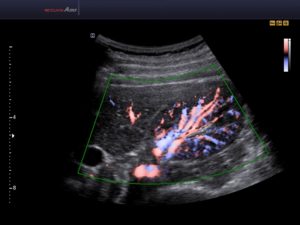

Данные исследования передаются на монитор компьютера, и расшифровываются медицинским специалистом. Существует спектральная допплерография и визуализационная. Первая передает оценку состояния кровотока в виде кривой линии, вторая – в виде наглядной картинки в цветном или черно-белом варианте.

Цветовое разрешение показателей, иначе цветовое допплеровское картирование (ЦДК) имеет большую информативность, поскольку, фактически, исключает ошибки при диагностике. Красным цветом на мониторе отображается кровоток, направленный к датчику, голубым – движение кровотока от датчика. Яркость цвета определяется скоростью процесса тока крови.

ЦДК, как вид УЗИ, основанный на Допплеровском эффекте, позволяет оценить сосудистый кровоток. Основой ЦДК является сочетание черно-белого изображения в УЗИ-диапазоне и оценки тока крови по допплеру.

Когда аппарат установлен в режим ЦДК, врач может видеть на мониторе обычное УЗ-изображение. В той его части, которая изучается, в цвете даны скорости потока крови.

Способы цветной кодировки картограммы следующие:

- оттенками красного цвета кодируют скорость кровотока, движущегося по направлению к датчику;

- оттенками голубого – скорость тока крови, движущейся от датчика.

Цветное допплеровское картирование дает врачу возможность максимально точно рассмотреть характеристики кровотока в почечных сосудах, с использованием цвета

Чем менее насыщенный цвет, тем, соответственно, меньше скорость. Кроме того, на мониторе отображена оттеночная шкала и ее расшифровка (описание соответствия оттенка-скорости).

ЦДК визуально отображает и анализирует: направление, скорость и характер потока крови, проходимость, сопротивление и диаметр изучаемого сосуда.